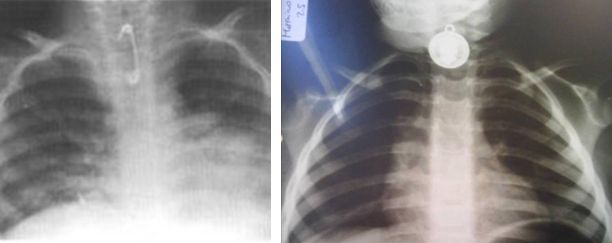

ASPIRACIÓN DE CUERPO EXTRAÑO EN NIÑOS.

La asfixia es la obstrucción en la vía aérea o impedimento de la respiración por un cuerpo extraño,   incluyendo la faringe, hipofaringe, y la tráquea. La obstrucción de las vías respiratorias puede ser mortal, si el impedimento es completo, ya que conduce a un deterioro grave de la oxigenación y la ventilación.

Alimentos, monedas y juguetes son las principales causas relacionadas con lesiones de asfixia y muerte.

La vía aérea del niño tiene un diámetro más pequeño por lo tanto es más probable que se obstruya en forma significativa con pequeños cuerpos extraños.